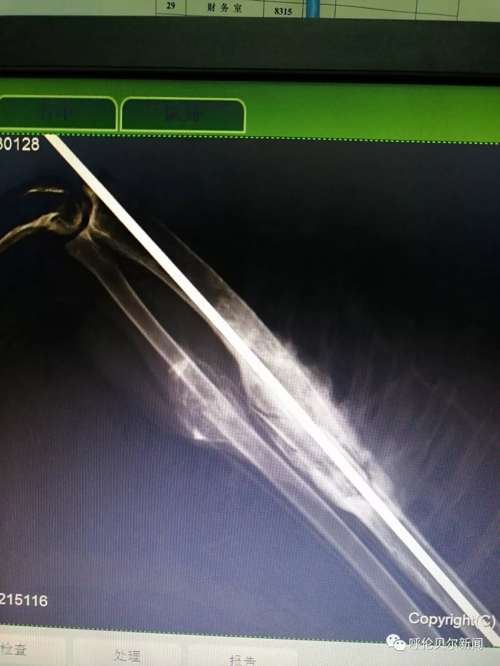

“我折了,希望有好心人能救助我!”2018年8月25日中午13:54分,双龙发了第一条关于这只雕鸮的微信朋友圈。“医院给雕鸮拍了x光片,发现右尺骨和桡骨两处骨折。身边没有能给宠物做手术的医生,我把图片发到朋友圈求助,咨询我市多名专家,他们都说桡骨非常细而且骨头很脆很难固定,手术难度太大。”双龙说。 “伤口感染,羽毛上的血渍结成了块,鸟的眼神里满是警惕和无奈,草原猛禽的风姿不再,可怜巴巴的样子,很让人心疼。”一直跟踪采访的新右旗融媒体中心记者巴图毕力格说。 >>>2018年8月31日 一边精心喂养,一边筹集为雕鸮治疗的资金,并通过微信群等方式寻找医生。经一名台湾野生保护志愿者联系,8月31日,双龙联系了毕业 于中国农业大学动物医学院、中国执业兽医师张拥军医生。 “我是一只国家二级保护动物雕鸮,我受了很重的伤,幸运的是我遇到双龙老师和张医生,他们没有放弃我……”一段雕鸮自述在腾讯公益被转载,很多野生动物保护志愿者解囊相助。5232.46元的爱心款向巴尔虎草原汇集。

在北京的张拥军医生看了X光片后表示可以进行手术,但是现在跨省运输国家二级野生保护动物审批手续繁琐时间太长,为了能够尽快手术,张拥军医生决定在海拉尔“出诊”。几经周折,双龙在海拉尔找到具备做手术条件的玩皮宠物医院,这家医院不仅同意免费提供手术场还表示愿意提供各种手术器具和药品。

>>>2018年9月3日 9月的草原日渐苍凉。清晨,双龙带着雕鸮行程300多公里来到海拉尔。一场秋雨让海拉尔这座城市清新怡人。玩皮宠物医院手术室内,来自北京的张拥军医生为雕鸮做了手术,海区几家宠物医院的医师均前来做助理、观摩学习。“手术难度比较大,术后休养也很重要,我会尽全力完成的。”张拥军医生结合20多年的临床经验,为在场的技术人员讲解手术要领。手术期间,记者进入手术室,看到双龙一边给张医生做助手,一边用蒙语安抚雕鸮。

经过近3个多小时的紧张繁忙,手术顺利完成。 经过一夜的观察,雕鸮各项体征趋于正常,9月4日上午,双龙带着雕鸮返回新右旗精心喂养。 >>>2018年9月14日 “拆线第二天,雕鸮状态良好,食量大增,每天能吃1斤肉,快养不起你啦!”双龙的朋友圈总会发一些动态,让关心雕鸮的人了解它况。